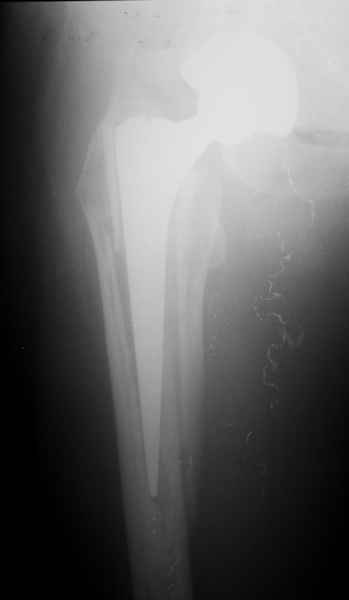

1.Остеосинтез на ножке. Мне кажется, что применительно к этому случаю малоперспективный вариант. Синтез хорош, когда можно его выполнить в малоинвазивном исполнении и достигнуть стабильности. Действительно, если ножка б/цементной фиксации после этого не будет иметь фиксации, то ревизия не будет иметь проблем. В представленном случае стабильность синтеза сомнительная, а проведение доп.иммобилизации приведет к контрактуре суставов.

2. Применение ножки дистальной фиксации, мы отдаем предпочтение ножке Вагнера с фиксацией проксимального отдела на ножке. Более травматичное вмешательство, но при стабильной фиксации ножки реабилитация идет в обычном режиме.

Хочется показать два подобных случая, П-ка З. 72 лет и п-т Г. 80 лет. Сразу принимаю замечание, что это были ножки цементной фиксации, просто под руками не было бесцементника.